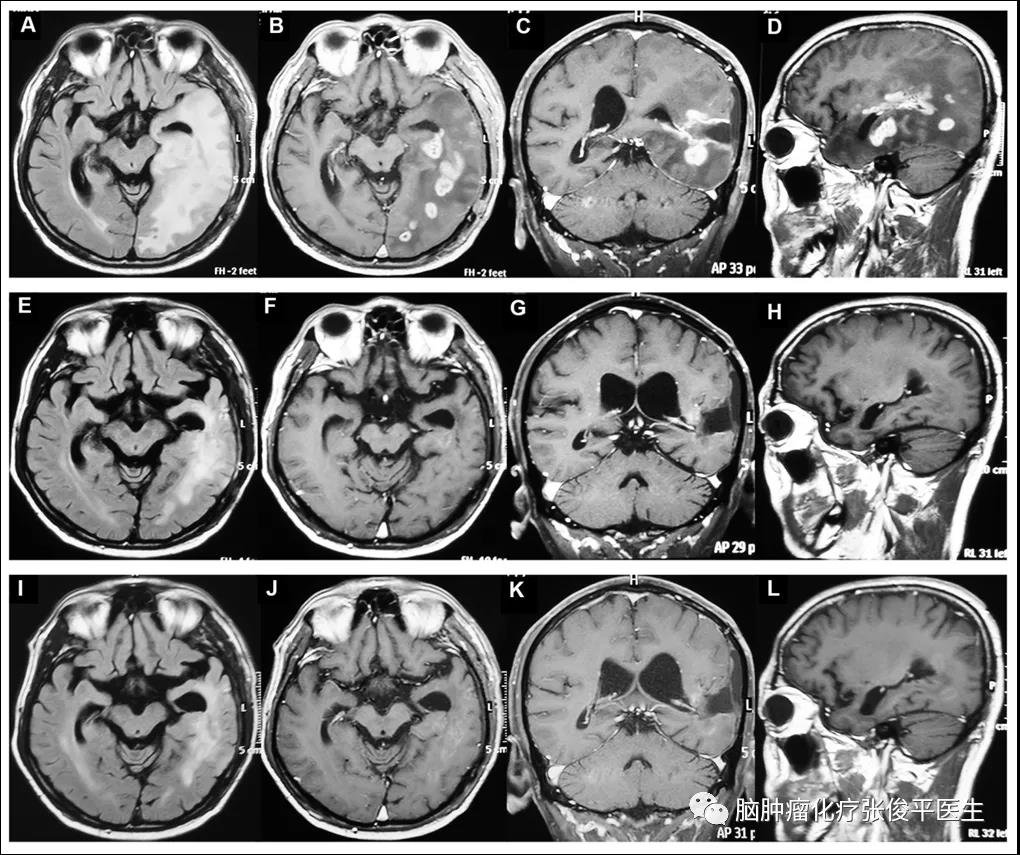

图2为1例CR患者治疗前后的核磁表现。经2个周期治疗后,强化肿瘤消失,非强化病变(Flair相)缩小(图2A-H)。经过3个周期的治疗后,核磁显示未复发,证实CR的疗效(图2I-L)。

图2. 一例获得CR的患者治疗前后的核磁表现:上行为化疗前;第2行为化疗2周期后,强化影消失;第3行为化疗3周期后,肿瘤无复发。